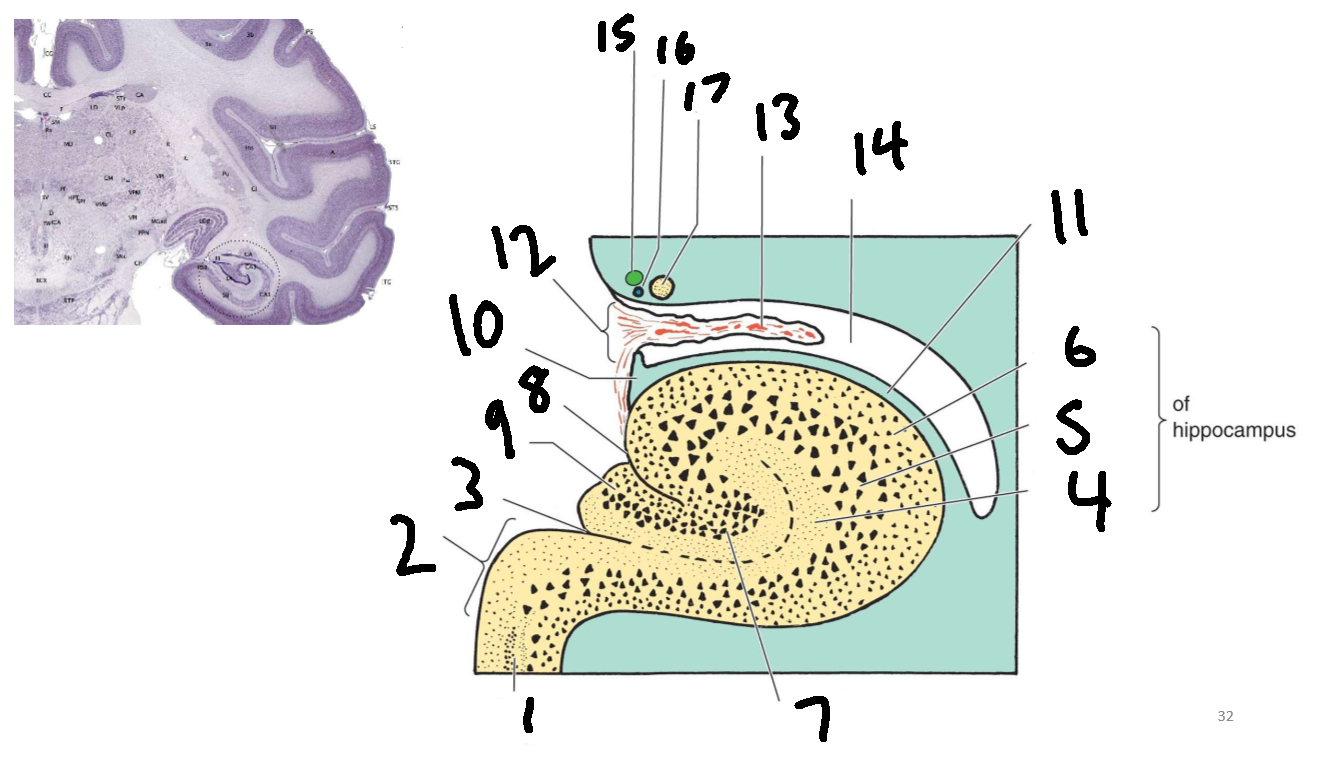

What is 1?

parahippocampal gyrus

What is 2?

subiculum

What is 3?

hippocampal sulcus

What is 4?

molecular layer

What is 5?

pyramidal layer

What is 6?

polymorphic cell layer

What is 7?

granule cell layer of dentate gyrus

What is 8?

fimbriodentate sulcus

What is 9?

dentate gyrus

What is 10?

fimbria of hippocampus

What is 11?

alveus

What is 12?

choroid fissure

What is 13?

choroid plexus

What is 14?

temporal horn of lateral ventricle

What is 15?

stria terminalis

What is 16?

thalamostriate vein

What is 17?

tail of caudate nucleus

What is the function of the hippocampus?

event based memory, episodic memory, declarative memory